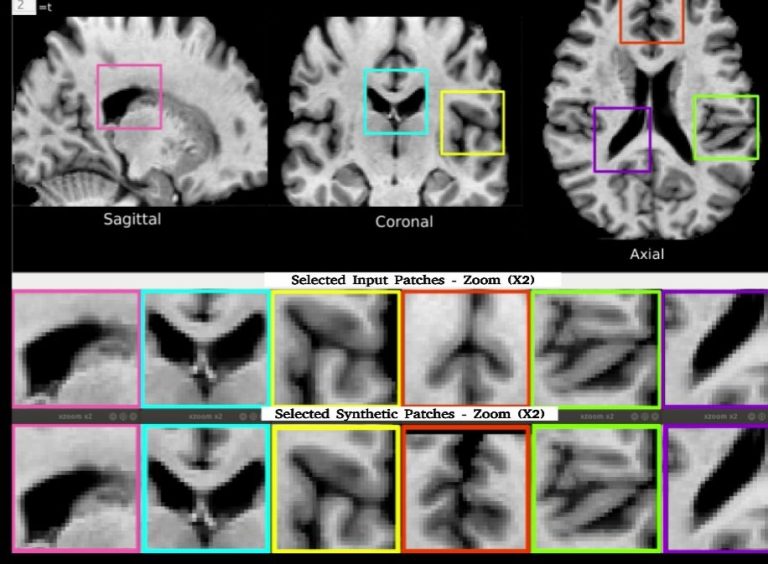

Rilevamento della Memorizzazione in Modelli Generativi per Imaging Medico

La diffusione di modelli generativi profondi ha portato alla creazione di dati sintetici per l’imaging medico, essenziali per ricerca e…